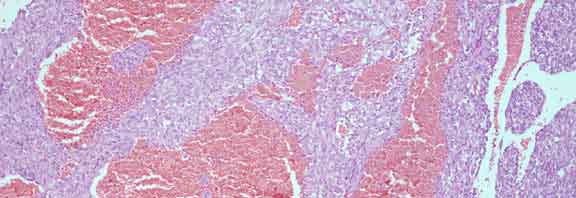

Mass on right auricle (x100)